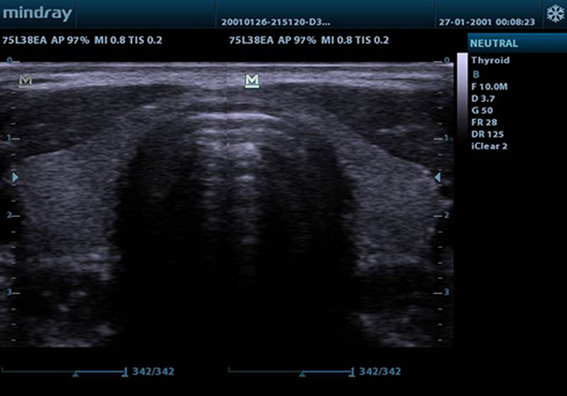

ExFOV

untuk mendapatkan informasi diagnostik yang lebih baik melalui gambaran struktur anatomi yang diperluas pada semua probe convex dan linear.